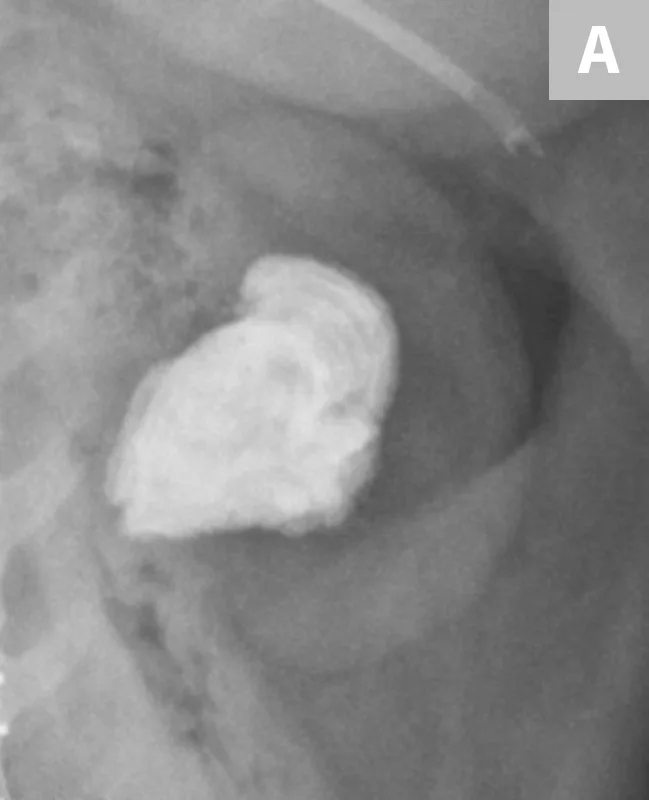

FIGURE 8A

Lateral radiograph of the urinary bladder in a dog with a confirmed calcium oxalate calculus. This calculus has a very irregular margin often seen with calcium oxalate calculus formation.

The lower detection rates for survey radiography are largely due to the variations in the chemical composition of different calculi. The most common types of calculi in small animal practice are struvite and calcium oxalate; both are mineral opaque (Figure 8).13,14,16,17